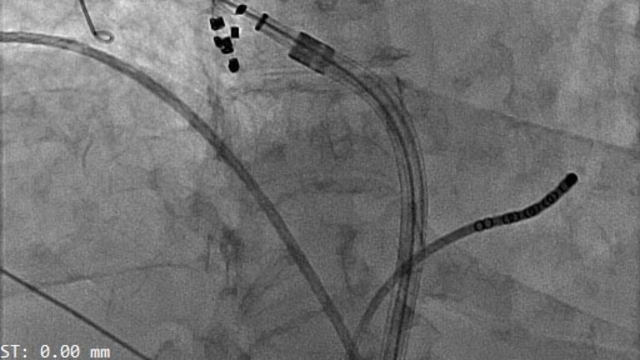

Operasyonu gerçekleştiren Eskişehir Şehir Hastanesi Kardiyoloji Bölümü Doç. Dr. Mehmet Özgeyik, elektriksel ablasyon tedavisinin dünya genelinde 5 yıldır kullanıldığını söyledi. Kalpteki ritim bozukluğunda yaygın tedavinin hastalığa sebep olan dokuları yakma ya da dondurma gibi yöntemler olduğunu ifade eden Doç. Dr. Özgeyik, elektriksel ablasyonun daha kısa ve etkili bir tedavi yöntemi olduğunu ifade etti. Bu ameliyat yönteminin Türkiye’de bir kamu hastanesinde ilk kez uygulandığını kaydeden Özgeyik, “Hastamız, uzun zamandır olan ritim bozukluğu şikayetiyle bize başvurdu. Nefes darlığı ve çarpıntı gibi çeşitli semptomları mevcuttu. Uygun tedavi sonrası hastamızın şikayetleri hala devam ettiği için ‘ablasyon’ dediğimiz işlemi planladık. Yeni sistemle Türkiye’de ilk kez uygulanması yeni başlamış olan ve kamu hastanelerinde ilk kez uygulanan elektriksel yöntemle ablasyon dediğimiz işlemi uyguladık. Bu teknoloji dünyada yeni yeni uygulanmaya başladı ama 4-5 yıldır mevcut olarak var. Fakat ülkemize yeni giriş yapmaya başladı. Hastanemizde ilk kez uygulandı ve özellikle Sağlık Bakanlığı’na bağlı kamu hastanelerinde Türkiye’de ilk uygulanan merkez burası oldu. Yapılan işlem aşağı yukarı 1 saat sürdü. İşlem sırasında hastamızın ritmi normale döndü, bu bizim en çok sevindiğimiz durumdu. Kendisi de şikayetlerinin azaldığını belirtiyor” diye konuştu.